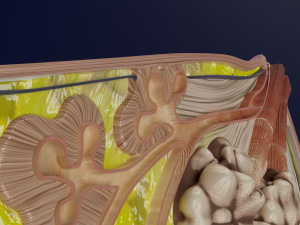

This is a 1:1 scaled model of right breast cut opened in sagittal plane to reveal its internal antomy and histology (schematic). The deeper parts and fascial layers are also depicted to give a very detailed approach to the model. The full layers starting from skin, nipple areola, till intercodtal muscles and ribs are also depicted.